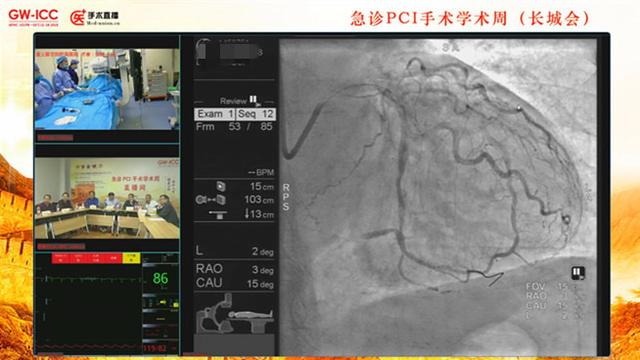

于是,在2017年和2018年的长城国际心脏病学会议上,董建增主导召开了急诊PCI学术周,开创了急诊手术直播讨论的创新性模式。

2017年长城会上急诊PCI连续转播24小时,共转播急性心肌梗死急诊PCI 34例,观看转播人次超过10万;在2018年为期4天的学术周上,全国80余家医院报名参与,共转播手术57台,观看转播人次超过100万。

与以往有精心准备的手术交流不同,急诊介入手术直播是突发性的,不知道会遇到什么情况的患者,对前方医生和讨论专家都更具挑战性,但收获也更多。参与过学术周的多家医院表示,这对他们提升医生水平,优化流程、持续改进,颇有成效。